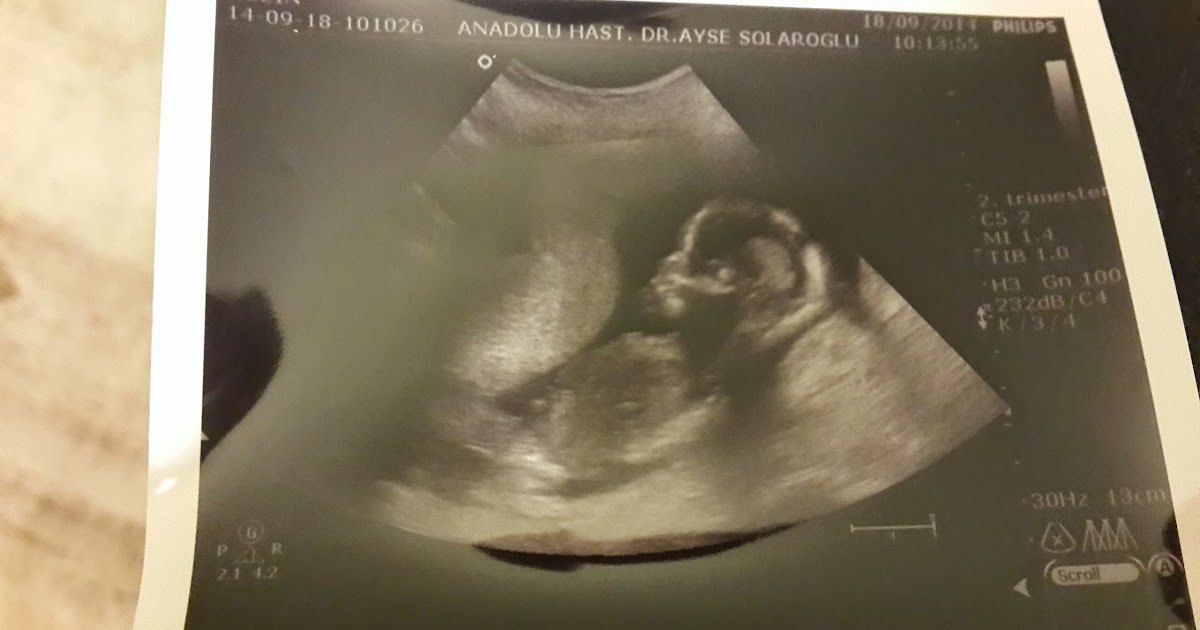

Ultrasonda Gebelik Kesesi Ne Zaman Görülür

Dün keseyi gördük fakat bebeği göremedi doktor birşeyler görüyorum ama vajinal ultrasonla baksak görülür ama hiç gerek yok daha görmeyi beklemiyorum erken.

Bu durum boş gebelik yani sahte gebelik geçirdiğinizi aslında hamile olmadığınız anlamına gelebilir. Sağlıklı bir gebelikte kese, vajinal ultrasonla 4. Tahminine gore 7 haftalik hamileyim dun gittim plesenta gorunuyor fakat bebek yok dedi cumartesi tekrar cagirdi suan tehlikede yok dedi ama cok endiseleniyorum cumartesiye kadar bebek gelisirmi acaba. Merhaba beta 3302 çıktı 5 haftalık hamileyim ancak kanamam var ara ara doktorum beni korkuttu bebek duşucek diye doğruluğuna. 5 haftalık bebek ultrasonda görünür mü 5 haftalık hamileyim kese var bebek yok 5 haftalık hamileyim ultrasonda görünmüyor. Hamilelik, yumurtanın spermle döllenmesi sonrasındaki 5 günde bölünmeye devam etmesi ve rahim duvarına yerleşmesi ile başlamaktadır.